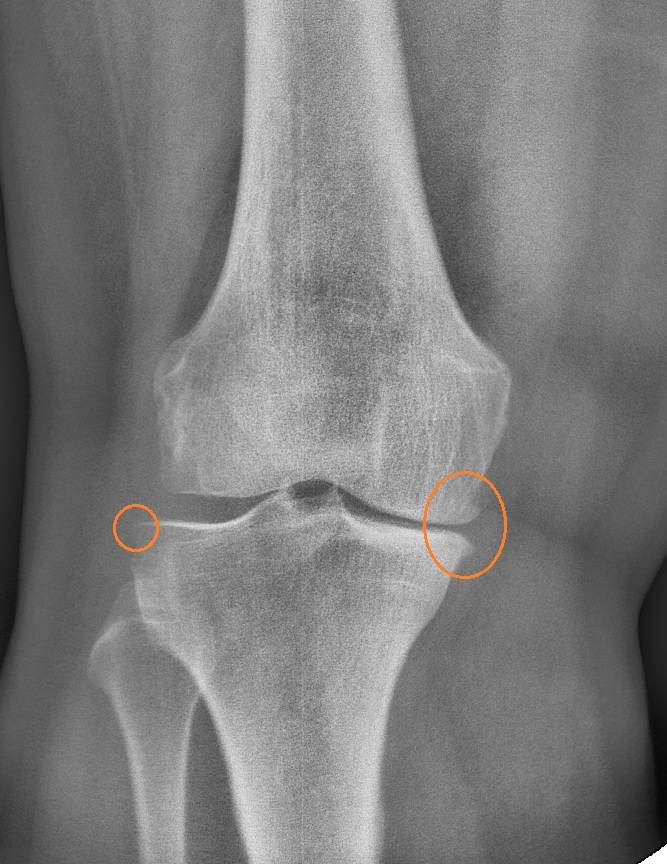

Рентгеновские снимки остеосклероза костной ткани